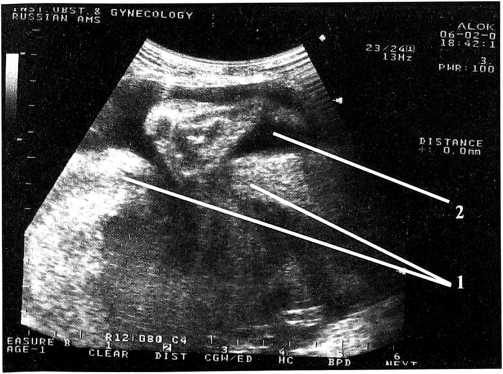

В матке определяется один живой плод в головном предлежании. По фетометрическим данным соответствует 30/31 неделям беременности. В верхней трети передней стенки матки имеется дефект миометрия 6,0×5,0 см. За пределами матки определяется часть амниотической полости 8,0×5,0 см, в котором находится петля пуповины, при шевелении в него выходит ножка плода (рис. 1,2).

Рис. 1. Ультразвуковая сканограмма: 1 — миометрий передней стенки матки; 2 — плодный пузырь и ножка плода вне полости матки